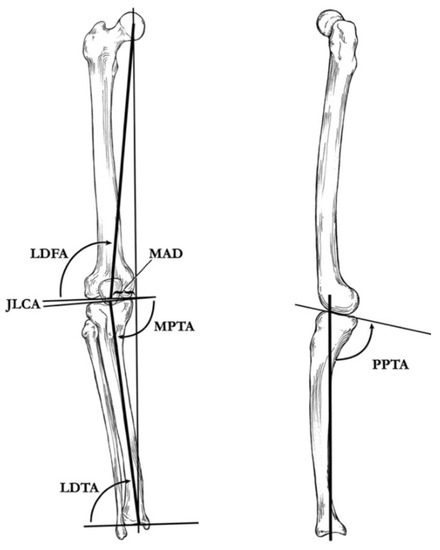

4. Radiographic Imaging

5. Radiographic Analysis

10. Surgical Planning